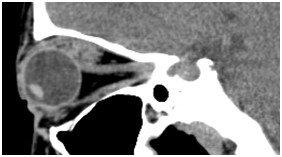

颞骨及耳(病例-前庭导水管扩大)